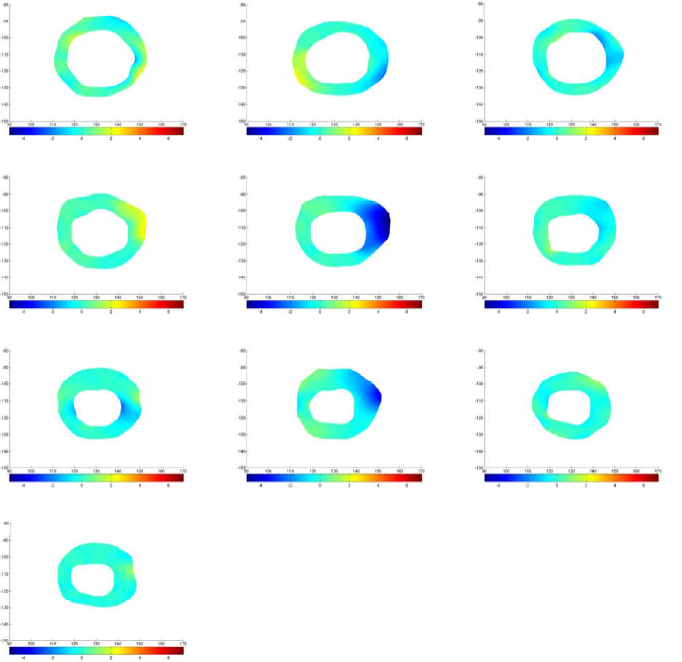

Fig. 11 shows the approximate infarct localization for the MI subject based on the comparison between normal and MI subjects’ effective strain during the cardiac cycle. Since the circulatory system of heart is determined very well, it is possible to make reliable conclusions about the problem that caused MI based on expert diagnosis and using these comparisons.